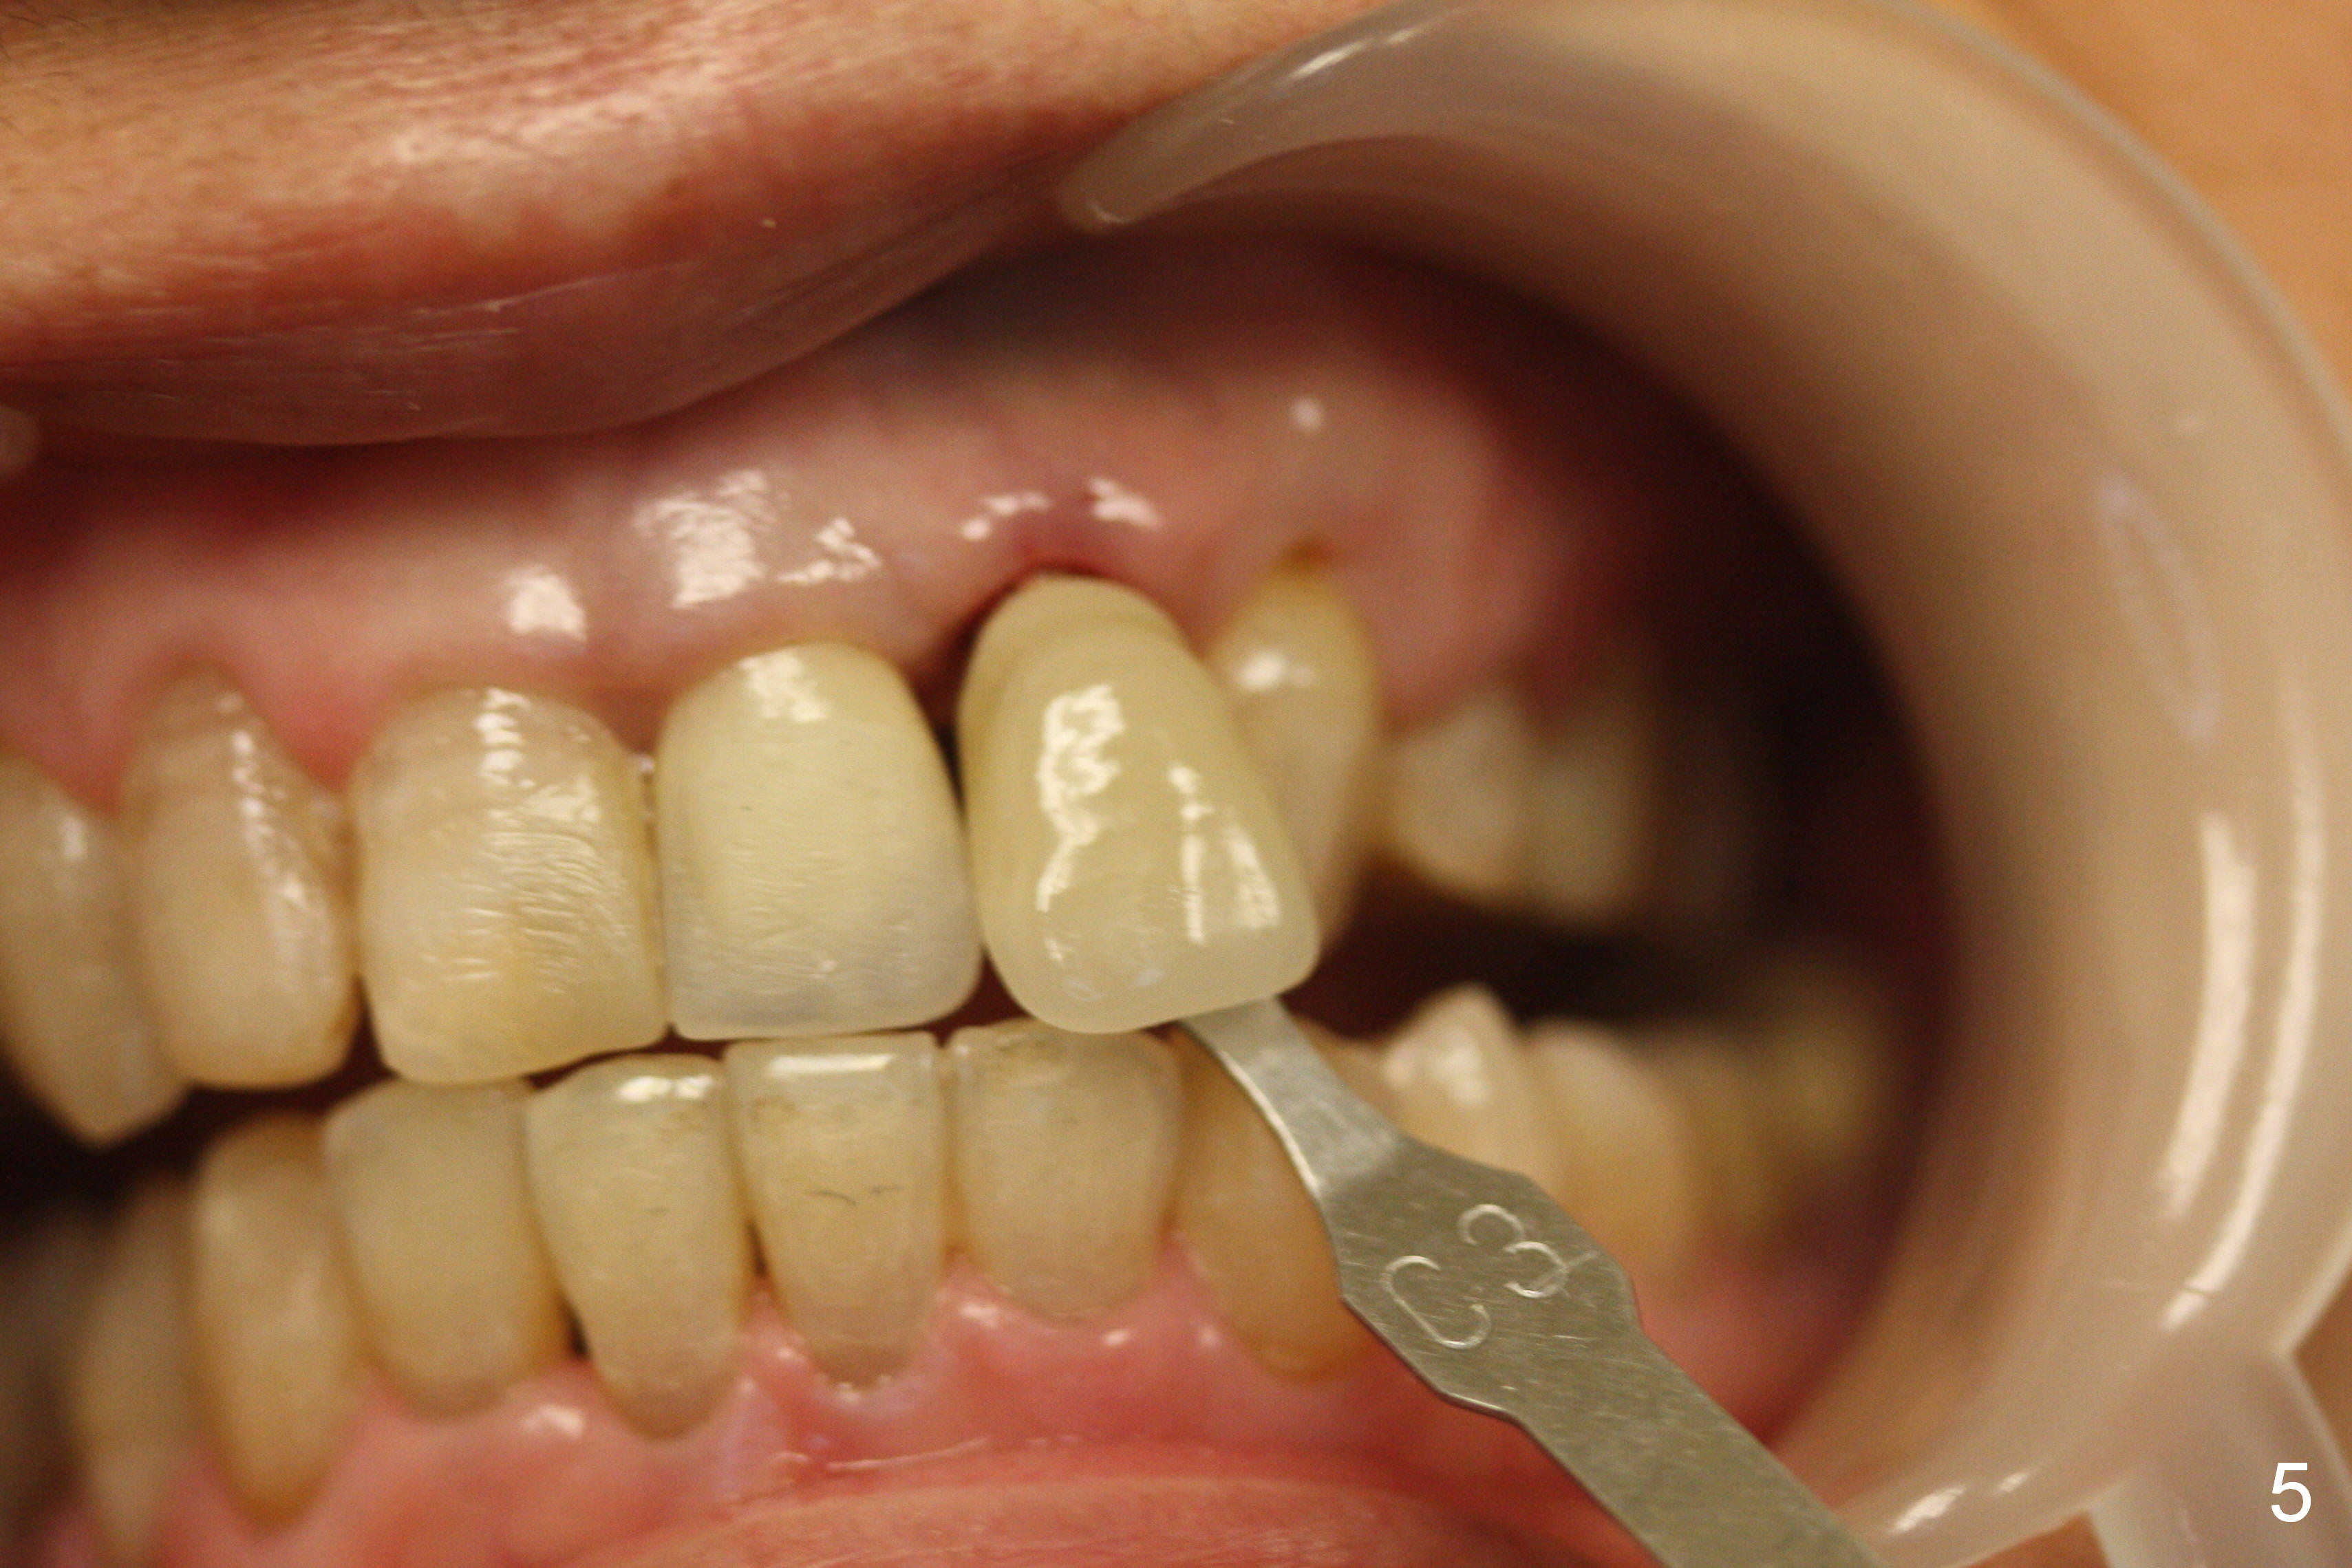

Placement of implant at the site of #10 is complicated. The trajectory is not ideal. Even though a 25 ° angled abutment is used, the abutment is still too buccal. Since the implant is placed deep (Fig.1,2), the margin is high (Fig.3). The margin of the crown should be thin and able to cover the Cavit as much as possible (Fig.3 C).